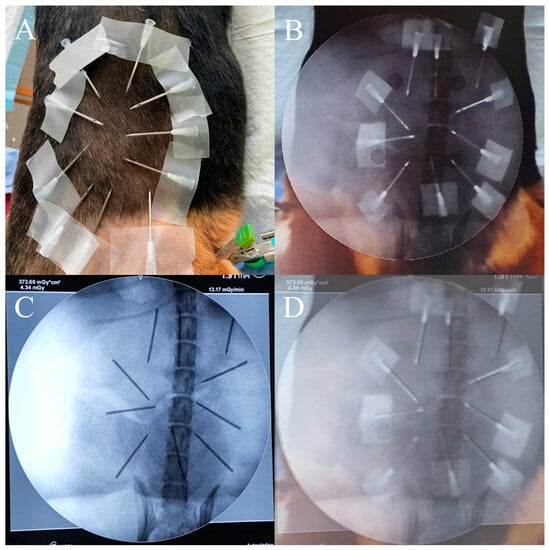

To evaluate the precision of the AR radiograph superimposition, 10 needles were fastened on the beagles’ backs and sides (Figure 5A). The positions of the needle tips in the AR radiographs were captured (Figure 5B). Radiographs were obtained to capture the real positions of the needle tips in the real radiographs (Figure 5C). We overlaid the AR radiographs (including real needles and AR spine) with the real radiographs (including needles and spine in the radiographs) by registering them through the spine, and the positions of the needle tips in the AR radiographs and in the real radiographs were compared (Figure 5D). The distance error of the needle tip and the angle error of the needle were measured. A total of 20 experiments were completed. For each group, 10 syringe needles in the AP radiograph and the lateral radiograph were evaluated.

Figure 3. Noninvasive fiducial markers. The fiducial markers can be visualized in the videos (A) and the radiographs (C); the AR-MISS system could automatically recognize the fiducial markers in the videos (B) and the radiographs (D).

Figure 5. Accuracy evaluation for AR radiograph superimposition. (A) Ten needles were fastened on the beagle’s back. (B) The position of the needle tips in the AR radiograph. (C) The position of the needle tips in the real radiograph. (D) The fusion display to compare the position error.